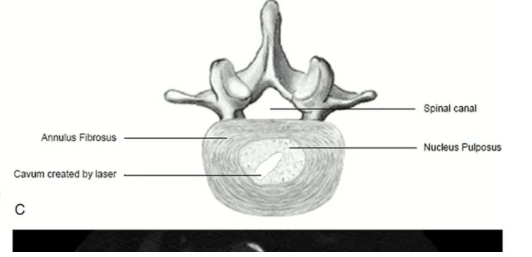

Perkutánní laserová dekomprese meziobratlové ploténky (PLDD) je minimálně invazivní zákrok, který využívá laserovou energii ke snížení tlaku uvnitř ploténky. Tento postup účinně ulevuje od bolesti způsobené vyhřezlou nebo vyklenutou ploténkou.

Pod lokální anestezií a s pomocí zobrazovacích metod lékař zavede tenkou jehlu do postižené ploténky. Skrz ni je následně zavedeno laserové vlákno, které odpaří malé množství ploténkové tkáně. Tím se sníží tlak uvnitř ploténky a uvolní se tlak na nervy, což vede k úlevě od bolesti.